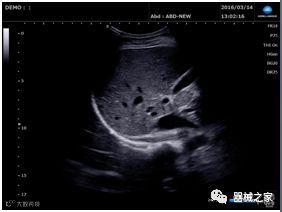

在RSNA 2018上发布的新成像被开发用于解决胎儿心脏和脑部成像问题。由于体积小且心率极快,因此难以进行详细的胎儿心脏评估。在18周时,胎儿的心脏大小与橄榄相当,每分钟跳动约150次。此外,结构本身非常复杂,婴儿不断运动,它始终是一个移动的目标。成像很重要,因为先天性心脏缺陷会影响全球每110个婴儿中的一个。

GE Healthcare用于胎儿超声的胎儿心脏和血管分析软件,在Voluson E10上提供,有助于在不到三分钟的时间内评估胎儿的心脏形状,大小和收缩性。称为辐射流的功能以三维视图显示血流。它还可以帮助显示缓慢流动的血液,例如神经血管循环。